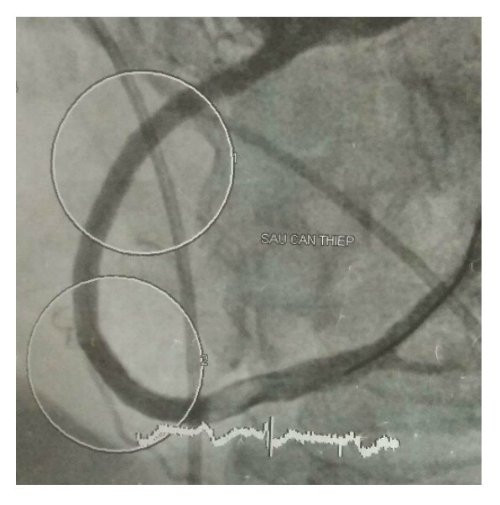

Hình ảnh chụp mạch máu của bệnh nhân sau can thiệp.